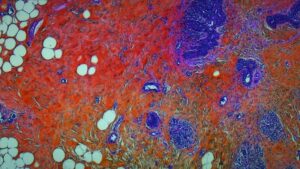

内臓も眼球も無修正で全部見せる!医者の愚痴まで丸聞こえの解剖ドキュメンタリー『人体の構造について』